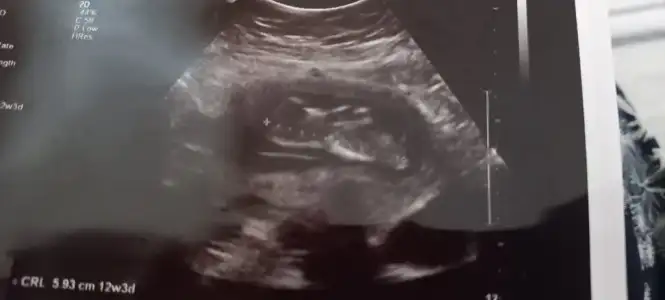

İkra meyra bunada bakarmısın lütfen 6 haftalık burda 😊

• IMG-20210612-WA0013.webp

IMG-20210612-WA0013.webp

47,2 KB · Görüntüleme: 53

• IMG-20210612-WA0012.webp

IMG-20210612-WA0012.webp

53,3 KB · Görüntüleme: 54